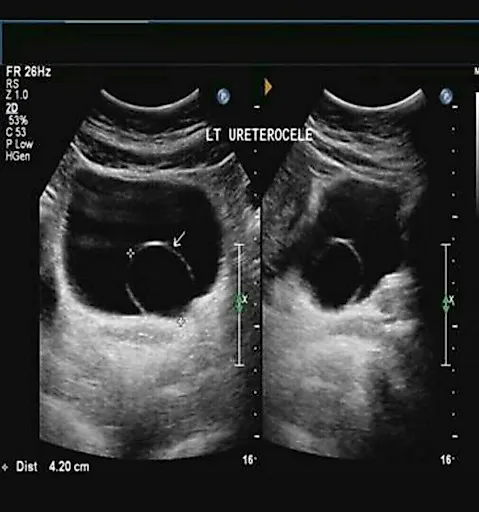

Мочевые органы и половые железы закладываются независимо друг от друга, но при дальнейшем развитии они формируют анатомически единую систему органов.Аномалии развития мочеполовых органов составляют более 30 % всех врожденных пороков развития.

Все аномалии развития почек создают условия для нарушения уродинамики, стаза мочи, инфицирования и развития тяжелых осложнений. Наиболее тяжелым осложнением у детей является пиелонефрит, при поздней диагностике которого развиваются деструктивные изменения в почке. Именно поэтому актуальными становятся ранняя диагностика и своевременная коррекция пороков развития органов мочеполовой системы.